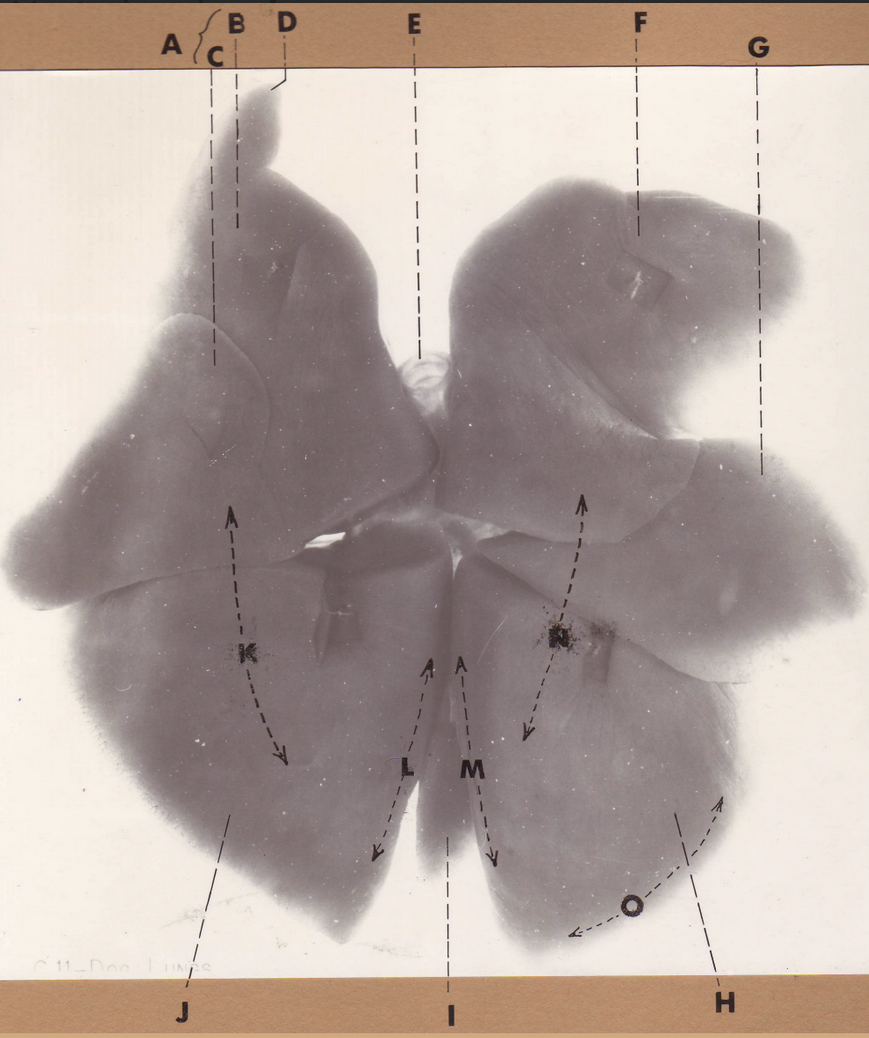

A

(pig lungs, dorsal)

L cranial lobe, caudal segment

B

(pig lungs, dorsal)

L cranial lobe, cranial segment

C

(pig lungs, dorsal)

trachea

D

(pig lungs, dorsal)

R cranial lobe

E

(pig lungs, dorsal)

cardiac notch

F

(pig lungs, dorsal)

middle lobe

G

(pig lungs, dorsal)

dorsal border

H

(pig lungs, dorsal)

costal surface

I

(pig lungs, dorsal)

basal border

J

(pig lungs, dorsal)

R caudal lobe

K

(pig lungs, dorsal)

L caudal lobe

A

(pig lungs, dorsal)

L cranial lobe, caudal segment

B

(pig lungs, dorsal)

L cranial lobe, cranial segment

C

(pig lungs, dorsal)

trachea

D

(pig lungs, dorsal)

R cranial lobe

E

(pig lungs, dorsal)

cardiac notch

F

(pig lungs, dorsal)

middle lobe

G

(pig lungs, dorsal)

dorsal border

H

(pig lungs, dorsal)

costal surface

I

(pig lungs, dorsal)

basal border

J

(pig lungs, dorsal)

R caudal lobe

K

(pig lungs, dorsal)

L caudal lobe